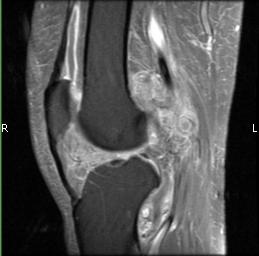

MRI (Fig. 1-10)

- Periarticular or synovial nodular mass with varying degrees of bone erosion.

- Nodular lesion with areas of hemosiderin (low signal on all sequences) and hemorrhage.

- On fat suppress images the tumor is high signal and hemosiderine cannot be seen.

- Joint effusions and bony erosions are well demonstrated. As with CT, contrast enhancement is typical.

Fig. 1-10: Magnetic Resonance of a PVNS of the knee shows a synovial mass with minimal bone erosion of the medial articular plate. On T1W and T2W images shows a tumor with low intensity areas (hemosiderin) and hemorrhage. Joint effusion is well demonstrated. Post contrast images demonstrate an irregular pattern of enhancement.